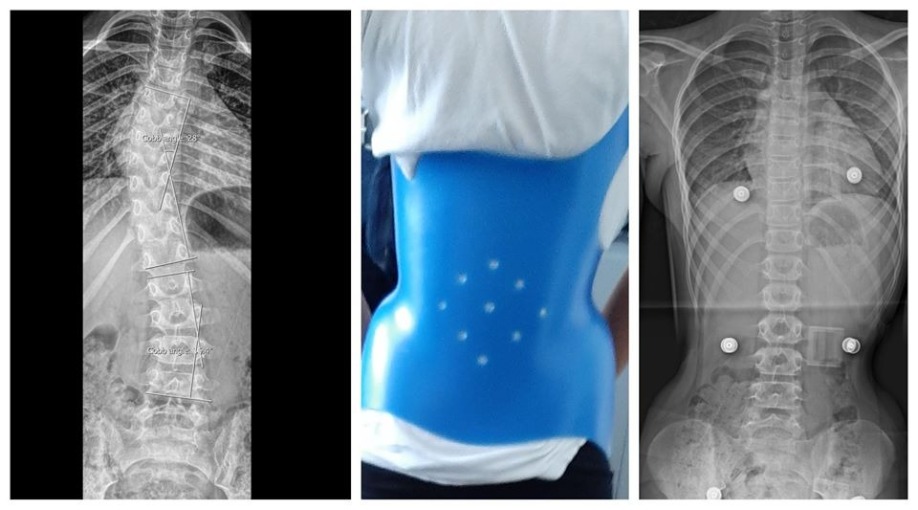

Η ιδιοπαθής σκολίωση είναι πλάγια κλίση και παραμόρφωση της σπονδυλικής στήλης, άγνωστης αιτιολογίας, η οποία παρουσιάζεται συχνότερα κατά την εφηβεία. Είναι πολύ πιο συχνή στα κορίτσια παρά στα αγόρια. Στην κλινική μας προσφέρουμε πρόγραμμα παρακολούθησης σε μια προσπάθεια να μειώσουμε την ανάγκη για χειρουργική επέμβαση. Η σκολίωση διαγνώσκεται με συγκεκριμένες ακτίνογραφίες που επιτρέπουν τη μέτρηση μιας συγκεκριμένης γωνίας (γωνία Cobb). Γίνεται διάγνωση σκολίωσης όταν αυτή η γωνία του Cobb είναι μεγαλύτερη από 10 μοίρες. Επιστημονικές μελέτες υποδεικνύουν ότι η χρήση εξατομικευμένου νάρθηκα στην αναπτυσσόμενη σπονδυλική στήλη σε ασθενείς με  σκολίωση μεγαλύτερη από 25 μοίρες, μπορεί να αποτρέψει την επιδείνωση της παραμόρφωσης και την ανάγκη χειρουργικής επέμβασης.

Η πιο κάτω εικόνα απεικονίζει περιστατικό του Δρ. Ζένιου με παρουσία σκολίωσης άνω των 25 μοιρών με αποτέλεσμα να τοποθετηθεί ειδικός νάρθηκας για την σκολίωση, με εξαιρετικά αποτελέσματα.